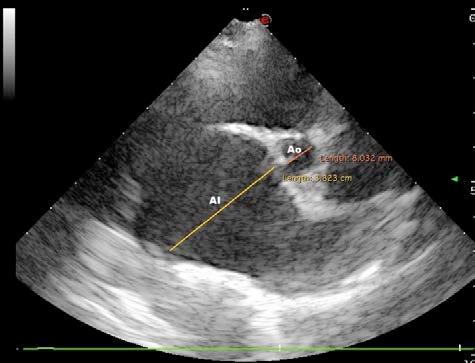

Diagnóstico por imagen Los hallazgos no son específicos de pacientes infecta dos con parvovirus. Las radiografías abdominales pue den ser normales al inicio de la enfermedad, o mostrar signos de íleo con distensión de asas intestinales por acúmulo de líquido o gas. Los signos ecográficos son asimismo inespecíficos, mostrando áreas de distensión con fluido y gas tanto en estómago como en intestino, íleo con movimientos peristálticos inefectivos, efusión peritoneal anecoica, etc.1,2,5,6 Ambas técnicas ayudan a descartar otras causas del cuadro clínico, como son cuer pos extraños, obstrucción e invaginación intestinal.1,2,5,6

Issuu converts static files into: digital portfolios, online yearbooks, online catalogs, digital photo albums and more. Sign up and create your flipbook.